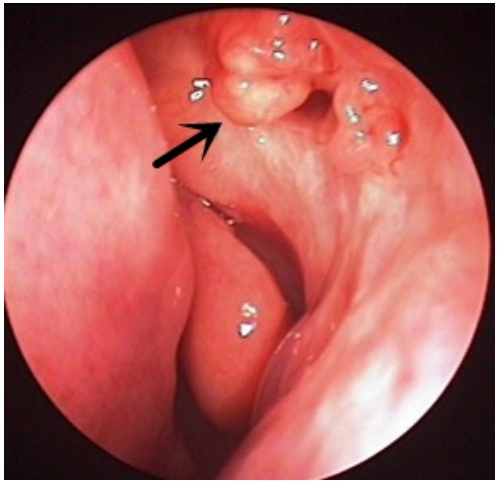

术后造瘘口肉芽组织增生26例31眼(26.96%),根据治疗方式分为物理清除联合TA局部注射组13例16眼和单纯物理清除组13例15眼,物理清除联合TA组的治愈率、好转率分别为93.75%、6.25%,物理清除组相应为60%、33.33%,组间比较差异有统计学意义(P = 0.026)。物理清除联合TA局部注射组患者的造瘘口转归良好(图5),所有病例治疗1 ~ 2次后均未发现肉芽组织复发。

图5 物理清除联合曲安奈德局部注射组患者造瘘口转归

Figure5 Outcomes of the ostium granuloma in excision combined with triamcinolone injection group